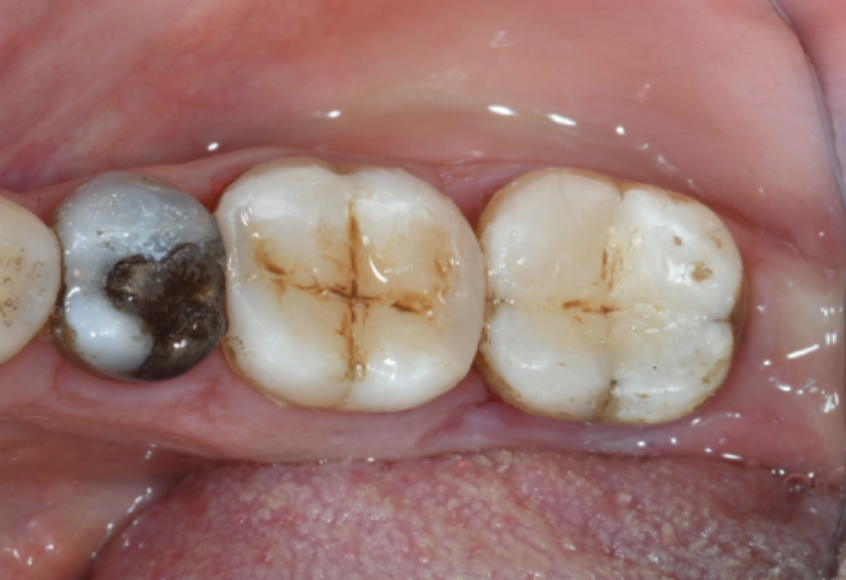

Radicular Cyst of Jaw: A Case Report